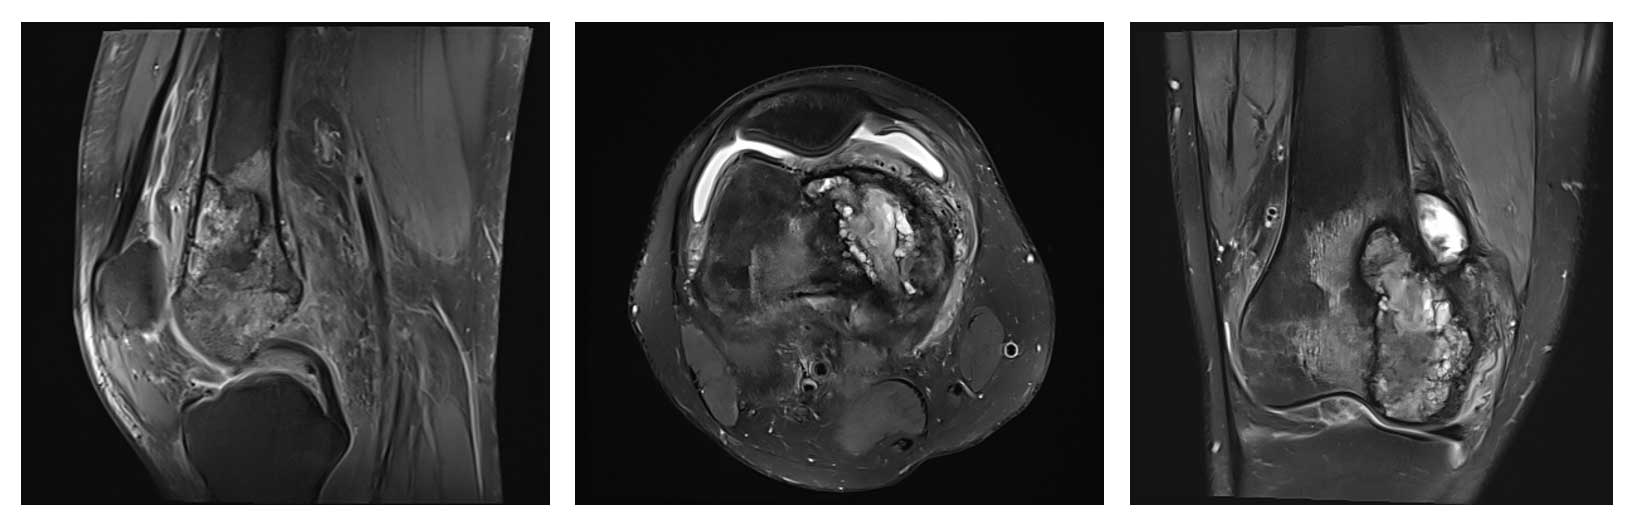

Ameliyat Öncesi: MR’da yumuşak doku komponenti ve çevreleyen ödem görülmekte.